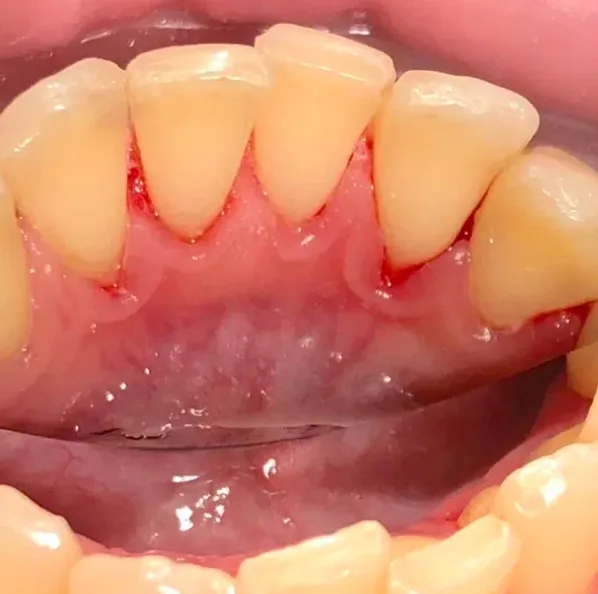

Выполнение профессиональной гигиены для снятия минерализованных зубных отложений и пигментированного налётаСмотреть работуСрок лечения:1 часСумма лечения:3 850 руб.

Процедура профессиональной гигиены для снятия минерализованных зубных отложений и пигментированного налётаСмотреть работуСрок лечения:40 мин.Сумма лечения:3 850 руб.

Процедура профессиональной гигиены для снятия минерализованных зубных отложений и пигментированного налёта.Смотреть работуСрок лечения:45 мин.Сумма лечения:3 850 руб.

Удаление десневых и зубных отложений с помощью УЗ-аппаратаСмотреть работуСрок лечения:60 мин.Сумма лечения:3 880 руб.